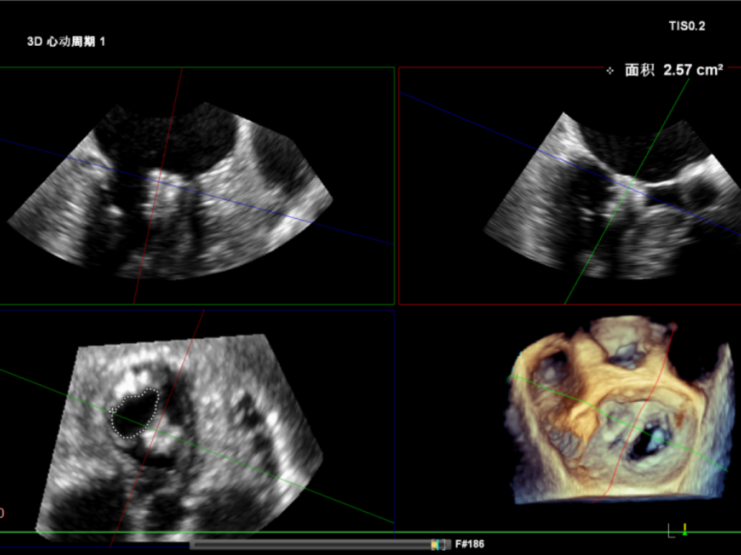

术前经食道超声显示:二尖瓣C1、P1区脱垂,重度关闭不全,彩色多普勒提示大量二尖瓣反流。术前瓣口面积MVA约5cm²,瓣环前后径AP约36.9mm,前叶A1约26mm,后叶P1约15.2mm。

术后即刻反流降为少量,剩余瓣口面积2.57cm²,平均跨瓣压差2mmHg。

术后复查超声心动图显示:二尖瓣轻度返流,三尖瓣中度返流,二尖瓣可见金属夹回声,启闭正常;各心室大小正常,升主动脉不宽,主瓣回声增强,启闭良好;二尖瓣舒张期峰值流速1.4 m/s,功能面积2.1 cm²,跨瓣平均压差约4 mmHg。